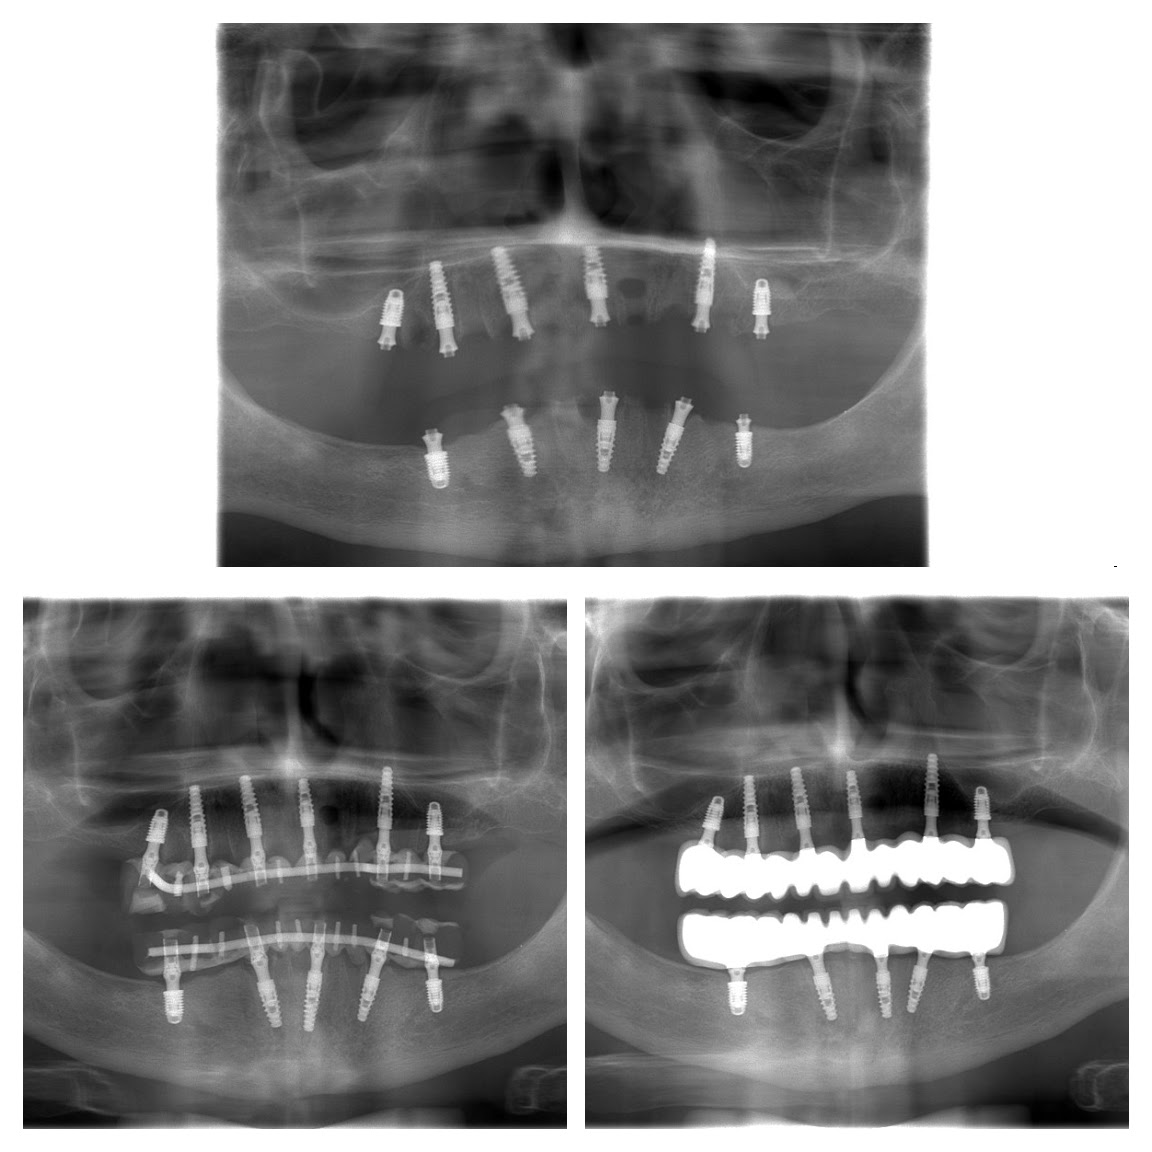

Aggi was one of our many “all on 5” and “all on 6” dental implant cases for both the upper and lower jaw that began in the second half of 2016 and completed in the 1st half of 2017.

As you can see from the photographs and x-rays, this was a relatively complicated case due to the lack of bone available (hence more implants being used). This is often typical of patients who have smoked in the past, had poor nutrition, suffered from serious illnesses, or simply a factor of aging.